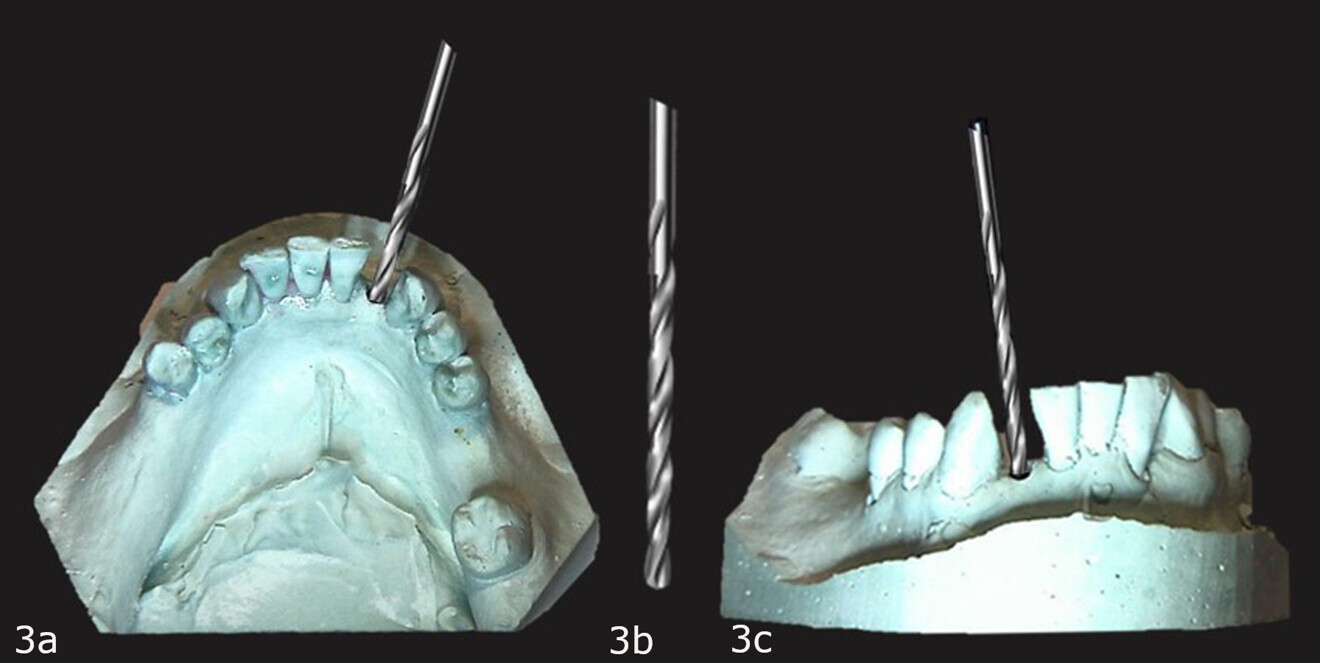

The modified guide post was inserted back into the guide hole in the cast with the top oriented to the lingual aspect, a 3.85 mm upper removable part was placed over the top of the modified guide post in the cast, and a guide sleeve was placed on the upper removable part with the cleat oriented to the lingual aspect (Fig. 15). Primopattern LC Gel was placed over the cleat and primosplint placed in a similar manner to when the diagnostic guide was fabricated and light-polymerised to complete the corrected surgical guide (Fig. 16).

Figs. 15a & b: Upper removable part placed over the modied offset guide post on the cast and the guide sleeve placed over it with the cleat to the lingual aspect (a), all on the cast (b).